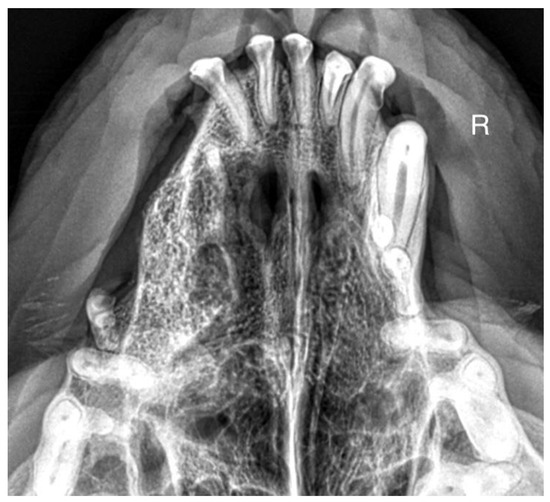

A 7-month-old male Rottweiler was referred for consultation because of severe swelling on the left side of the jaw, with a suspected jaw tumor. Clinical examination revealed no abnormalities in the aforementioned lymph glands and no soreness on palpation. Intraoral examination on the left side revealed severe asymmetry, with enlargement of the facial soft and hard tissues, an absence of permanent teeth, and buccal displacement of deciduous teeth. On the left side, rhinoscopic examination revealed normal anterior nostrils and a left nasal aperture with a lack of patency from the level of the nasal bony inlet to the posterior nostrils. A roentgenogram in the dorsal–ventral projection showed the presence of four ectopic teeth in the maxilla, with the formation of a dentigerous cyst (Figure 2). Using the CLP technique, the ectopic teeth were removed and the cyst walls were lanced. The bone loss caused by the cyst was 7.3 cm × 4.6 cm, and the jawbone left behind was too thin to provide a scaffold for the surrounding tissues and to ensure nasal cavity patency. From a 5 cm pellet of hydroxyapatite polymer material with curdlan previously soaked in saline (according to the manufacturer’s instructions), longitudinal flaps of 5 cm long, 1 cm wide, and 0.1–0.2 cm thick were cut and placed in the bony defect to strengthen the bony scaffolding of the jaw and nasal septum (Figure 3). The gingival flap was sutured with a single suture using 4-0 monofilament material. The first radiological follow-up was performed after 4 weeks, but due to the size of the defect and the size of the pellets of material used, the hydroxyapatite obscured the structures in the nasal cavity, preventing accurate assessment. A rhinoscopic examination revealed patency of the left nasal cavity. It was decided to conduct a radiological follow-up 6 months after the procedure, but the owner, for personal reasons, did not attend the follow-up appointment. After 12 months, another roentgenogram was performed, where a properly healed jawbone with closure of the cyst cavity could be observed. The nasal septum was formed properly, and the resulting bony scaffolding resulted in patency of the left nasal aperture, along with normal airflow on the left side (Figure 4).

Figure 2. X-ray in dorsal–ventral projection before surgery. On the left side, four ectopic teeth (marked with arrows) with the formation of a dentigerous cyst are visible.